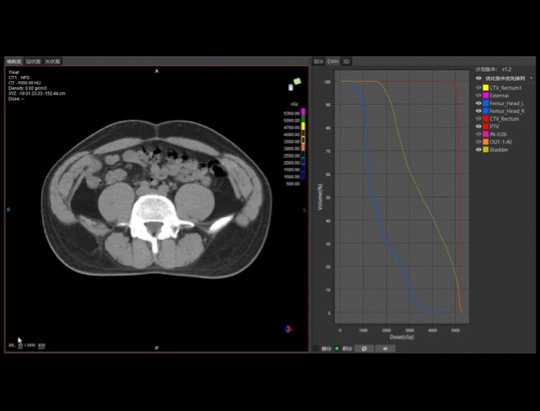

Z jednej strony niezbędne jest skrócenie czasu oczekiwania i zapewnienie pacjentowi jak najlepszych doświadczeń z leczenia. Z drugiej strony profesor Zhen napotyka w radioterapii wiele technicznych wąskich gardeł. Radioterapia jest uznawana za jedną z najlepszych metod leczenia nowotworów na świecie. Potrafi ona precyzyjnie zabijać komórki nowotworowe omijając zdrowe tkanki, co wymaga dostosowania leczenia do potrzeb każdego pacjenta, a także ścisłej koordynacji działań personelu medycznego w wielu obiektach i wykorzystania wielu urządzeń. Cały proces obejmuje sześć etapów: unieruchomienie pacjenta, symulowane pozycjonowanie, określenie obszaru docelowego, stworzenie planu radioterapii, kontrolę jakości planu, sterowanie obrazem i wdrożenie radioterapii. Każdy z tych elementów musi zostać przeprowadzony w bardzo rygorystyczny sposób, co wymaga czasu. „Czy można w fundamentalny sposób zoptymalizować ten proces, tak aby można było jednocześnie osiągnąć wysoką efektywność i precyzję?”- profesor Zhen przez lata szukała takiego rozwiązania.

W ostatnich latach, w związku z rozwojem sztucznej inteligencji w dziedzinie precyzyjnej radioterapii, profesor Zhang Zhen i dr Weigang Hu stworzyli zespół, którego celem było prowadzenie badań w zakresie inteligentnego określania obszaru docelowego oraz planowania radioterapii. Pod koniec 2019 r. szpital wprowadził do eksploatacji pierwszy na świecie zintegrowany aparat typu CT-linac produkcji UIH, łączący akcelerator liniowy ze służącym do diagnozy tomografem komputerowym. Pacjenci nie muszą już chodzić z jednego miejsca w drugie – cały proces radioterapii można przeprowadzić za jednym razem, na tym samym stole. Ponadto sztuczna inteligencja może przyspieszyć precyzyjne określenie obrysu guza i sformułowanie planu, co skraca wielogodzinny niegdyś proces do kilku minut, znacznie podwyższając efektywność zabiegów. Prof. Zhang Zhen uznaje to za punkt zwrotny: „jest to doskonałe połączenie działań badawczo-rozwojowych oraz projektowania produktu – jeżeli możemy w pełni zintegrować te dwa etapy w jednym procesie, to jest to przełom o podstawowym znaczeniu”. Dlatego profesor Zhen jest jedną z czołowych orędowniczek łączącej wszystkie etapy kompleksowej radioterapii All-In-One.

„Pomysł ten przetestowano po raz pierwszy 2 marca 2021 r. o godzinie 9.00: lekarze, fizycy i technicy zebrali się w pomieszczeniu sterowniczym, aby wykonać u pacjenta z rakiem odbytnicy pierwszy zabieg przy użyciu kompleksowej technologii radioterapii All-In-One. Kolejno wykonano pozycjonowanie symulacyjne TK, inteligentną modyfikację obrysu i przegląd, automatyczne planowanie, automatyczny reset, ocenę i przegląd planu, sterowanie obrazem TK, terapię oraz kontrolę jakości, czyli monitorowanie dawki w czasie rzeczywistym z użyciem elektronicznego detektora obrazowego (EPID). Cały proces został ukończony w 23 minuty, podczas gdy pierwszy zabieg radioterapii prowadzony w sposób tradycyjny zająłby co najmniej kilka dni. Jest to nowy model leczenia nowotworów z wykorzystaniem technologii sztucznej inteligencji, który otwiera nową erę inteligentnej terapii onkologicznej.”